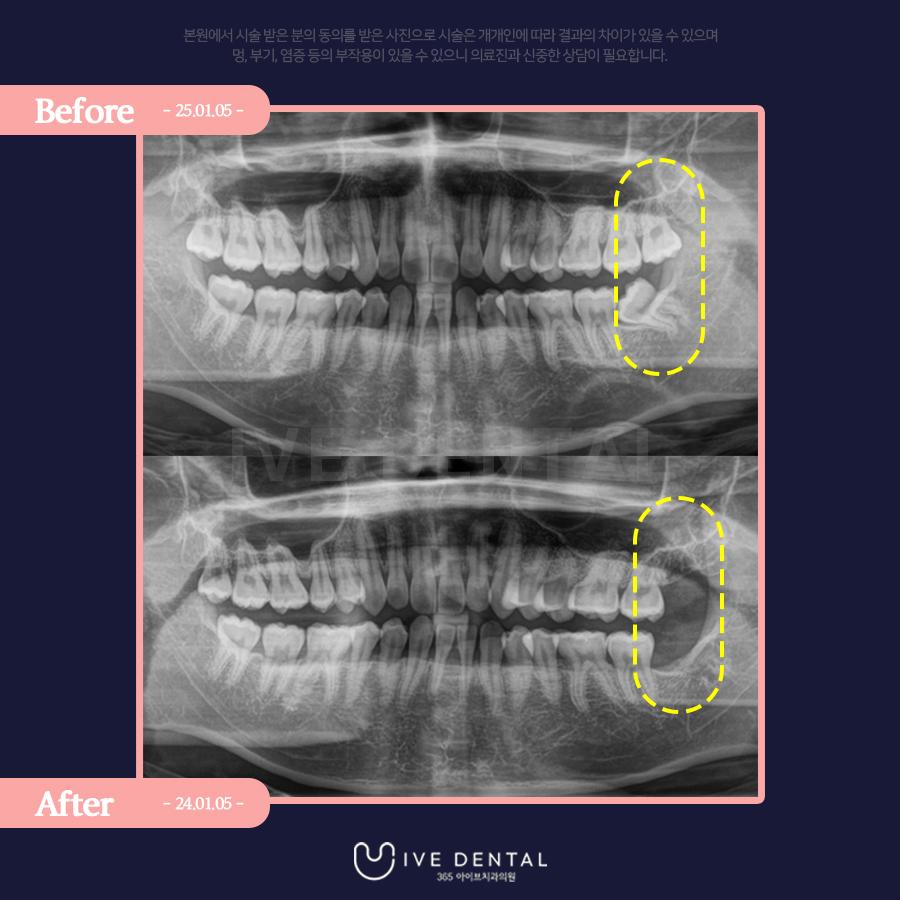

위 환자분의 경우에도 위쪽 사랑니가 깊숙이 박혀있으며 오른쪽 밑 사랑니는 아예 누워있는 형태입니다.

이런 경우에는 숙련된 의사의 발치가 꼭 필요한데요.

그러면 오늘도 환자분의 케이스를 한 분 소개해 드리겠습니다.

사랑니 발치를 위해 내원하신 20대 남자분이십니다.

사랑니가 양쪽에 모두 자리를 잡고 있어 발치를 원하셨는데요.

누워있는 사랑니도 보이네요.

아이브치과에서는 한 번에 4개 모두 발치도 전혀 문제가 없지만 환자분께서는 일

단 왼쪽만 먼저 발치를 원하셨습니다 .

왼쪽 위아래의 사랑니가 깔끔히 제거된 것이 보이시나요?

다음날 소독을 위해 내원하셔서 어떠신가 여쭤봤더니 통증이나 붓기도 전혀 없고 다른 쪽도 곧 발치하러 오시겠다고 하셨습니다!